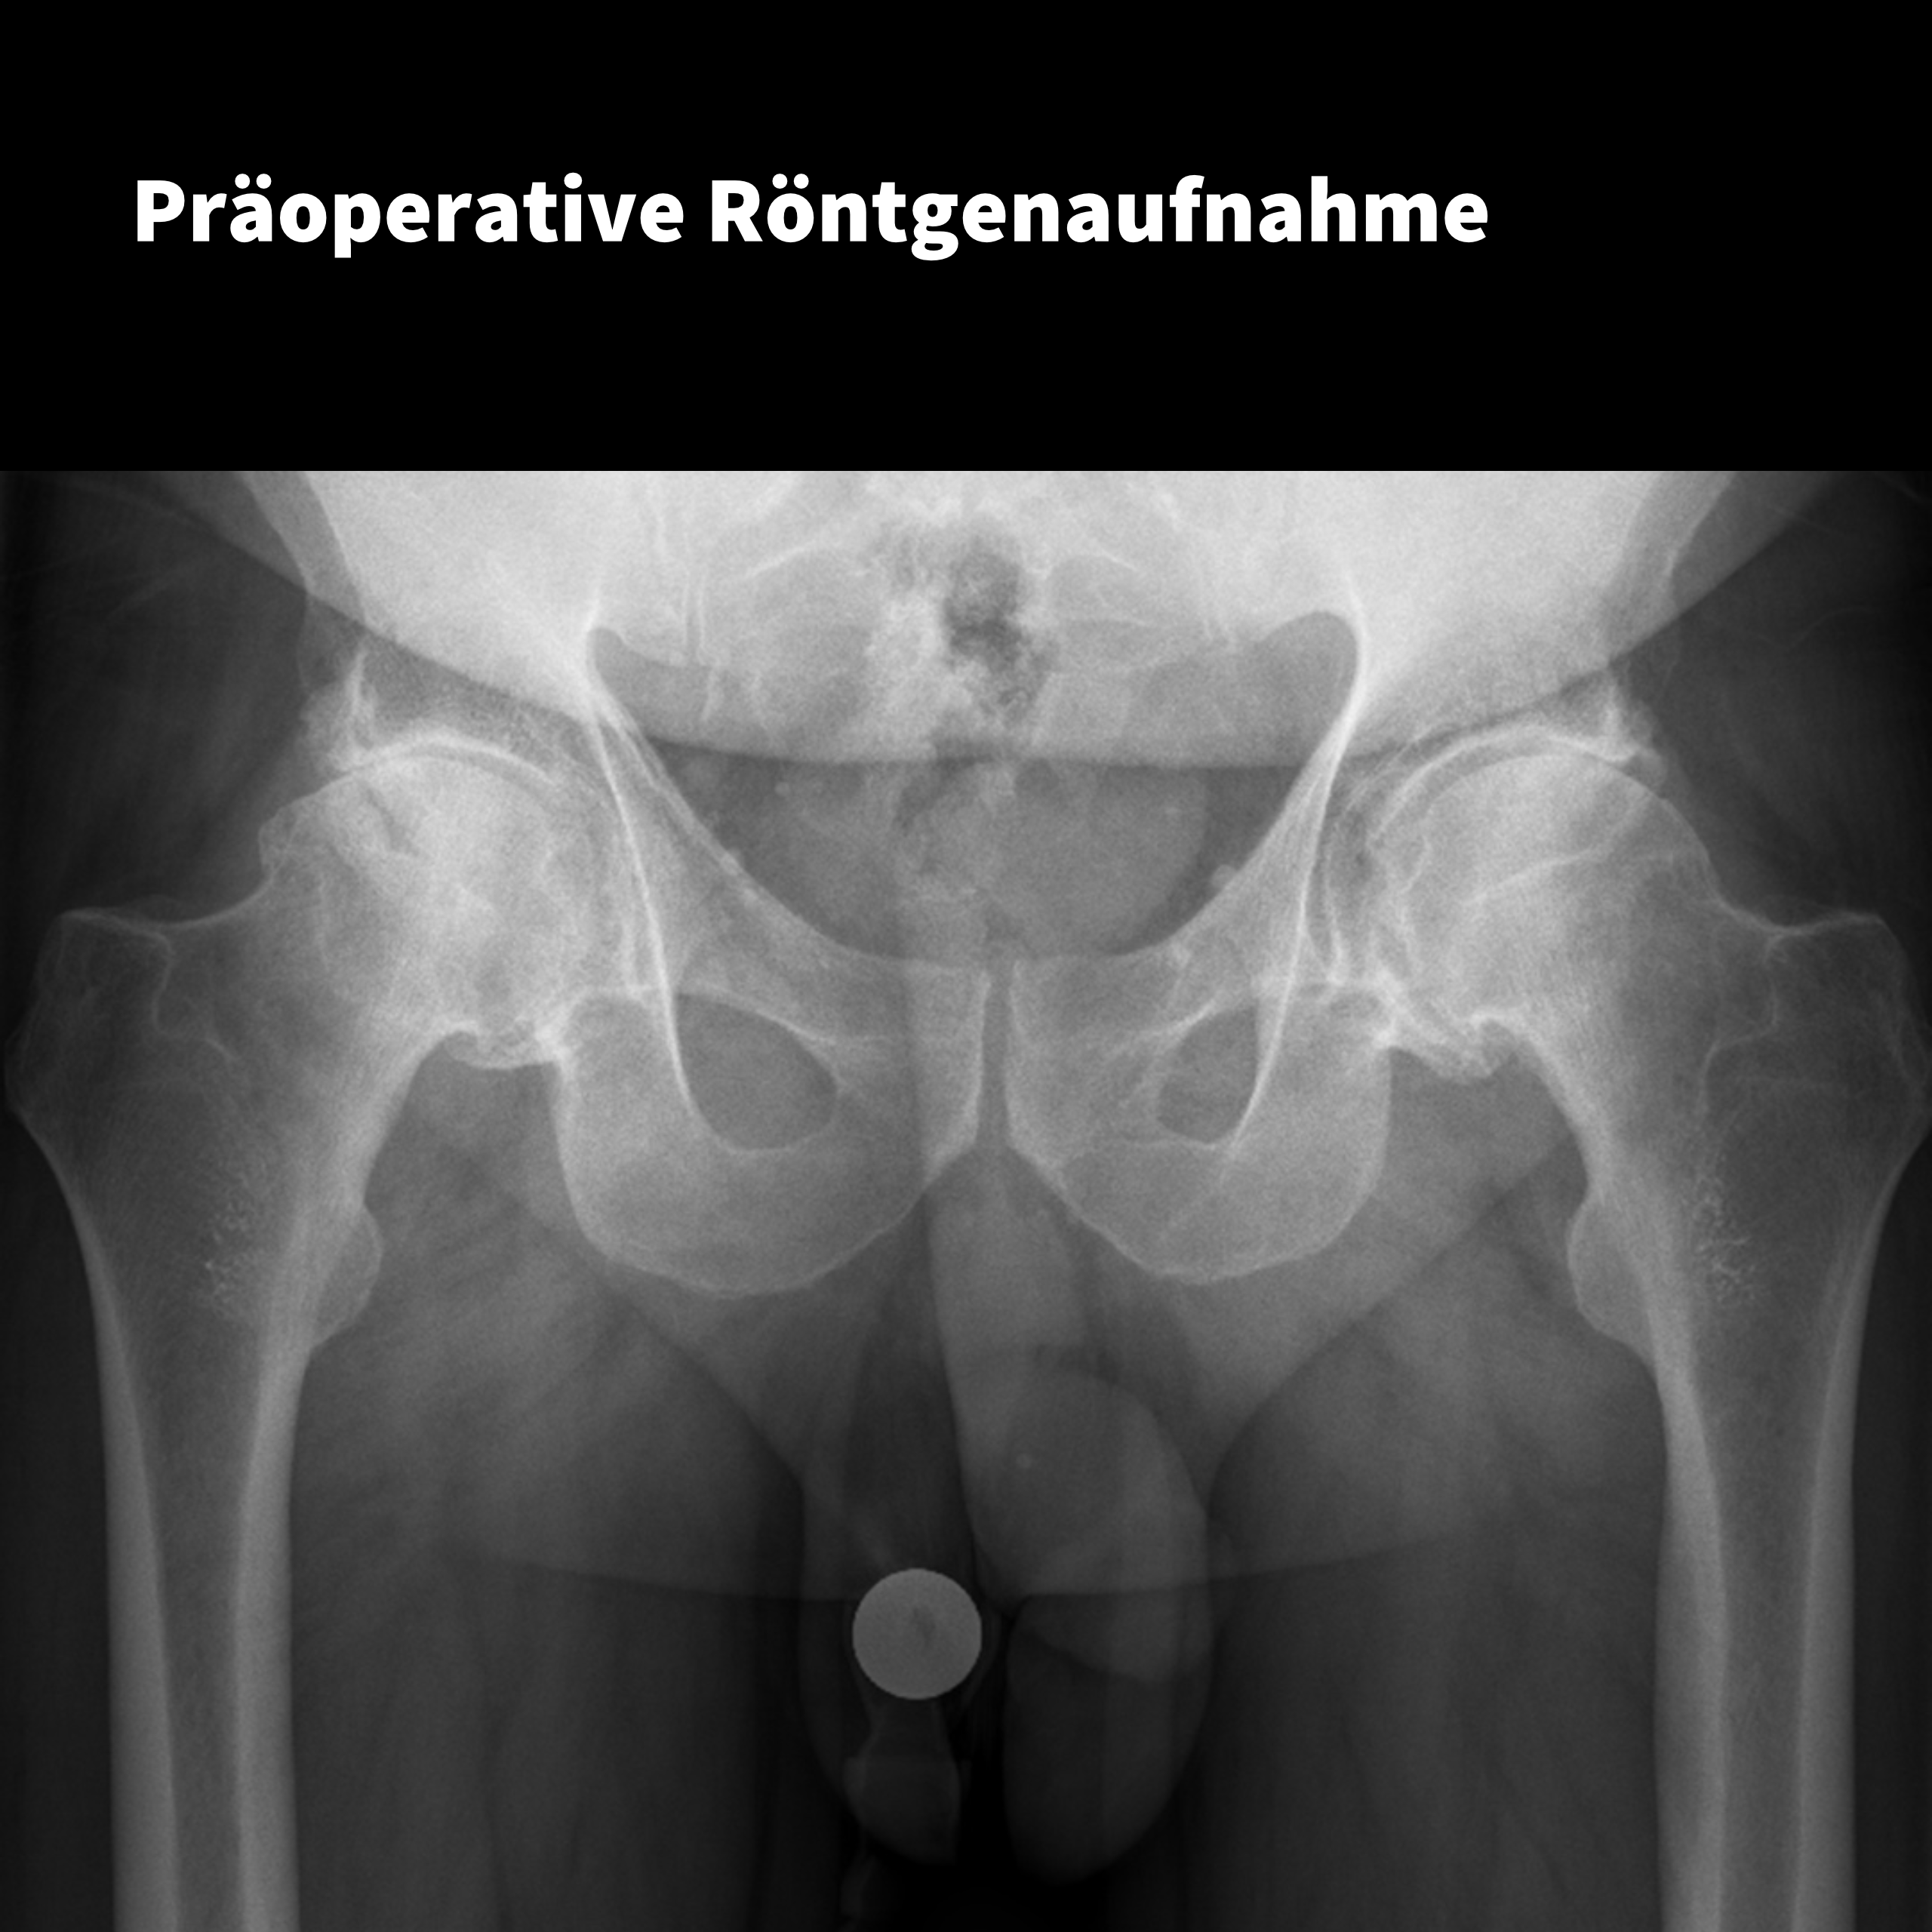

Beidseitige Kurzschaftversorgung

in einer Sitzung

Ein Fall von: Dr. Mumme Schüller, St. Josefs Hospital, Cloppenburg

Der Patient: Männlich, 62 Jahre